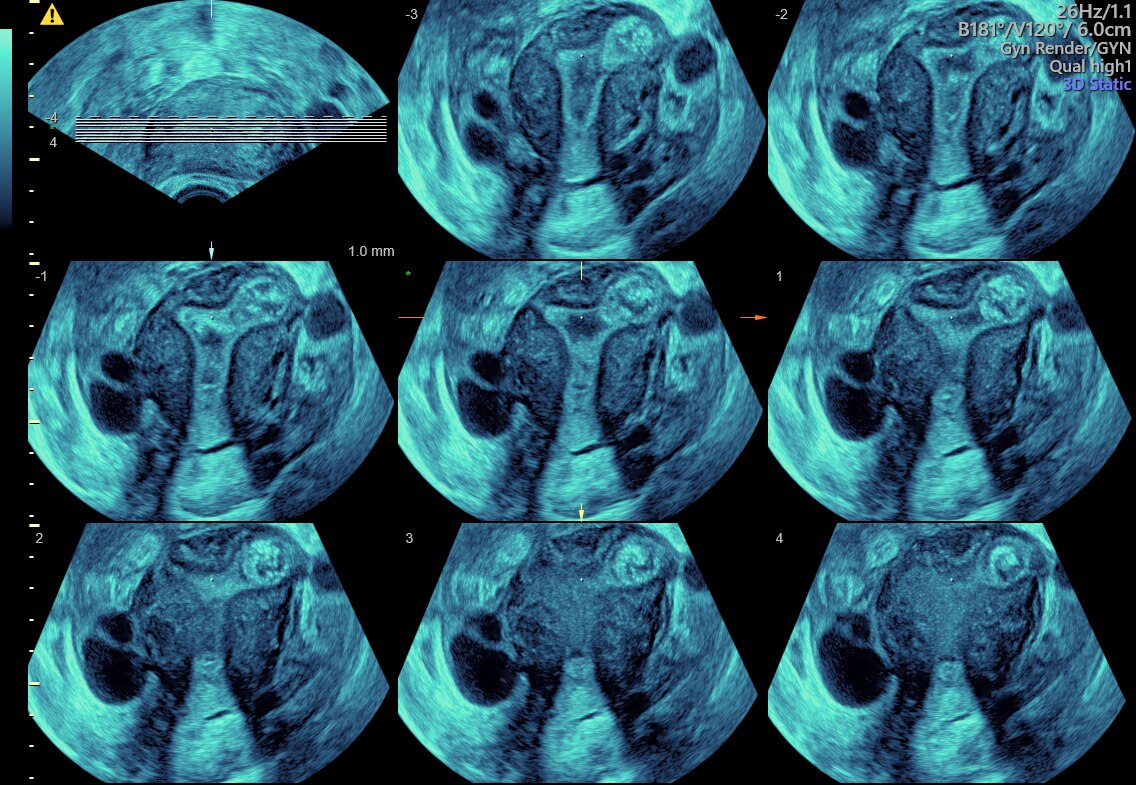

TUI (Tomography Ultrasound Imaging): Siêu âm cắt lớp

Tomographic ultrasound imaging (TUI) of uterine cavity